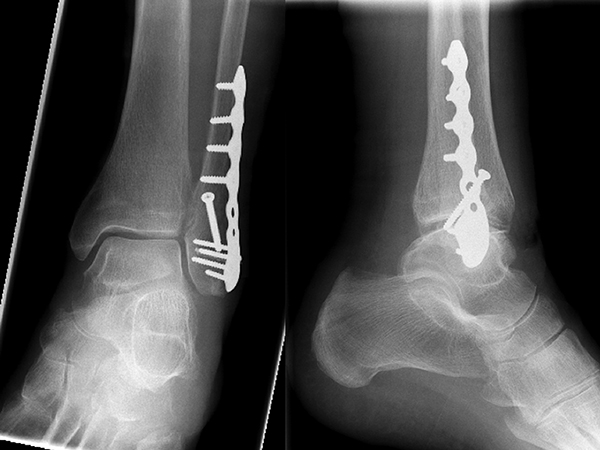

Bei multifragmentären Frakturen (AO 44-B2.3) oder bei schlechter Knochenqualität sollte die Versorgung mittels winkelstabiler Plattenosteosynthese erwogen werden (Abbildung 11 & 12).

Frakturen vom Typ AO 44-C werden in der Regel mittels interfragmentärer Zugschraube und Neutralisations-Plattenosteosynthese versorgt. Die Versorgung von Frakturen mit metaphysärer Trümmerzone (AO 44-C2) ist mitunter anspruchsvoll. Entscheidend ist die Wiederherstellung der korrekten Länge und Rotation der Fibula. Die Verwendung von winkelstabilen Implantaten bietet hier eine höhere Stabilität. Bei Typ C Verletzungen liegt definitionsgemäß eine Syndesmoseninsuffizienz vor, die entsprechend versorgt wird (siehe Abschnitt Syndesmoseninsuffizienz). Bei hohen Fibulafrakturen (AO 44-C3, Maisonneuve-Frakturen) steht die Versorgung der Syndesmoseninstabilität im Vordergrund. Eine zusätzliche Versorgung der proximalen Fibulafraktur ist nicht erforderlich.